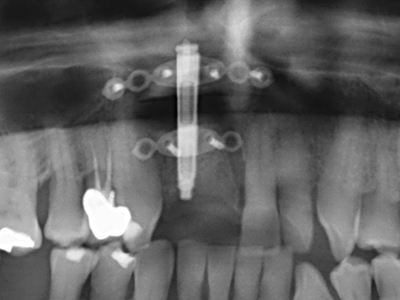

As shown in the past, basically any bone surgery procedure represents a possible indication for piezo surgery. Thus preparation of the mobile segment in distraction osteogenesis (Fig. 23-25) and sandwich osteotomy uses special attachments without endangering the blood supply to the crestal section, which is essential for the success of both techniques (Gonzalez-Garcia, Diniz-Freitas et al. 2008).

For removal of an implant, a vestibular bone cover that is replaced after removal of the implant screw can be prepared to retain the contour of the alveolar ridge.

There are additional applications in sinus surgery. Pathologies and foreign bodies can be removed from the sinus after concentric preparation of a generally trapezoid bone cover in the facial sinus wall. The bone cover is repositioned on conclusion of the intra-antral operation component and secured by wedging or adaptive sutures to prevent dislocation.